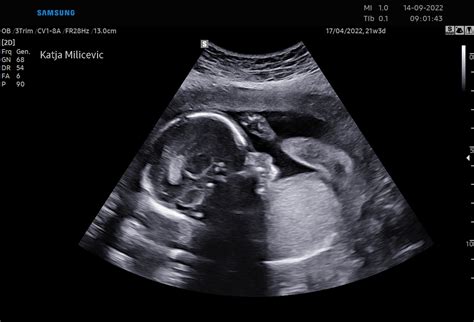

V 26. tednu nosečnosti otrok že dobro razvija svoje motorične sposobnosti. Dolg je približno 35-36 cm, kar je primerljivo z velikostjo buče špagetarice. V tem tednu se odprejo otrokove nosnice, kar pomeni, da lahko prvič "vdihne" plodovnico, s čimer se intenzivno urijo pljuča vse do rojstva. Prav tako se v tem obdobju razvije otrokov vid, saj so njegove oči že povezane z možganskimi predeli, ki so odgovorni za obdelavo vizualnih dražljajev.

Posledično postajajo gibi otroka v 26. tednu vse bolj opazni in raznoliki. Lahko zaznate brce, premikanje rokic, obračanje ali celo rahlo ritmično trzanje, ki ga povzroča krčenje diafragme ploda - znano kot "štucanje". Te gibi lahko postanejo še posebej izraziti, ko se nosečnica umiri, na primer zvečer ali med počitkom, saj takrat lažje zazna aktivnost otroka. Prav tako se lahko aktivnost poveča po obroku, kar je povezano z dvigom ravni sladkorja v krvi, ki vpliva na otrokovo energijo.